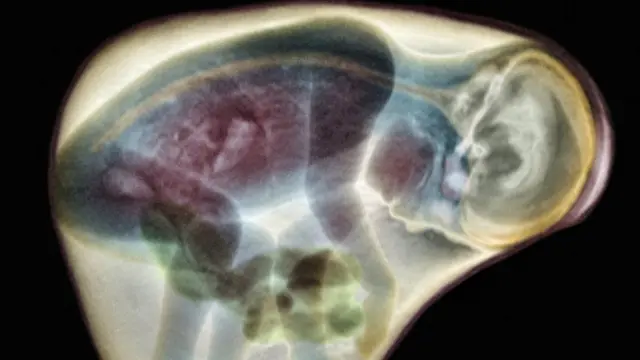

Şəklin mənbəyi, SPL